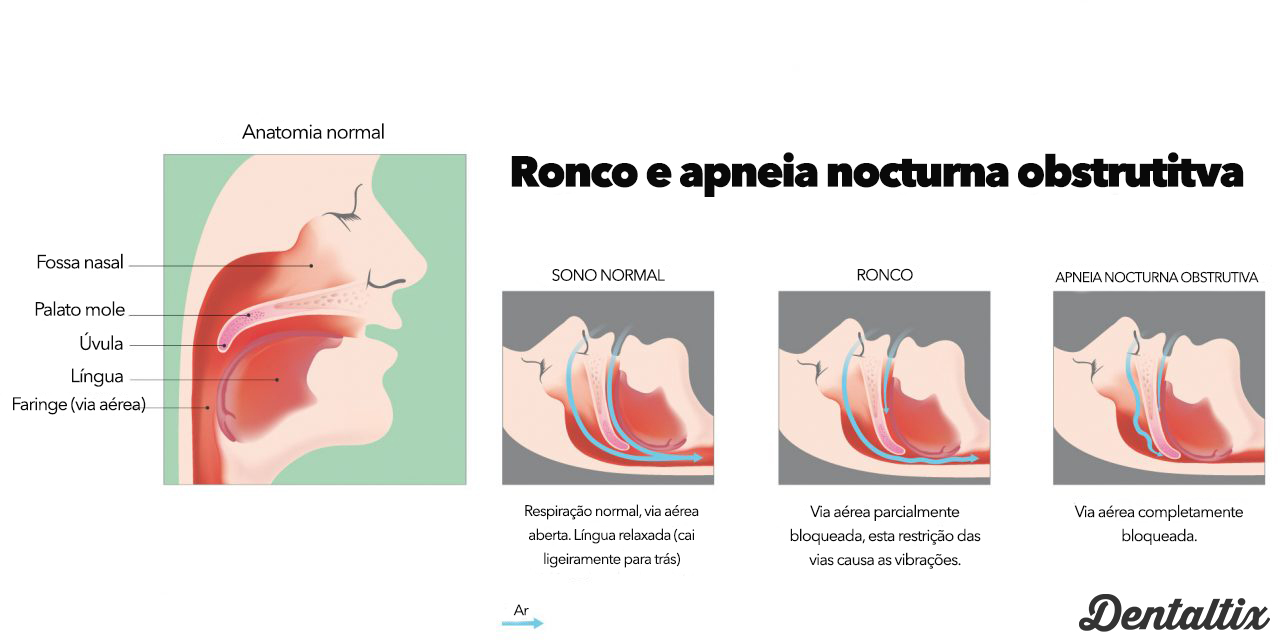

A Síndrome da Apneia Obstrutiva do Sono (Obstrutctive Sleep Apnea Syndrome, OSAS) é um

distúrbio do sono respiratório caracterizado por episódios repetidos de obstrução total ou parcial das vias aéreas superiores com sinais e sintomas que podem levar ao aparecimento de grandes disfunções sistémicas, causando redução na qualidade de vida.

Dispositivos orais (OD) ou aparelhos orais (OA) são uma das escolhas terapêuticas conservadoras para o tratamento sintomático da síndrome da apneia obstrutiva do sono (SAOS). São dispositivos intra orais nocturnos que estabilizam as primeiras vias aéreas e aumentam seus diâmetros, induzindo uma diminuição da colapsabilidade da faringe. Existem duas categorias de dispositivos intra orais para o tratamento de distúrbios respiratórios no sono: